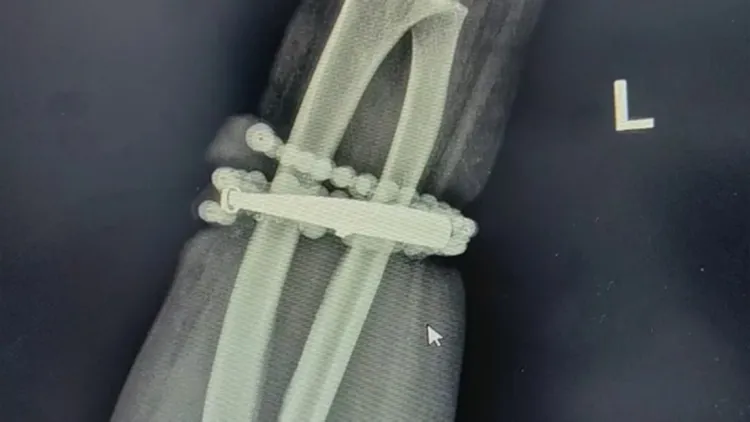

龚女就医后发现,手镯与串珠已经深深卡进手腕肉里,所幸经过1个多小时手术后顺利取出,并清创引流控制感染。